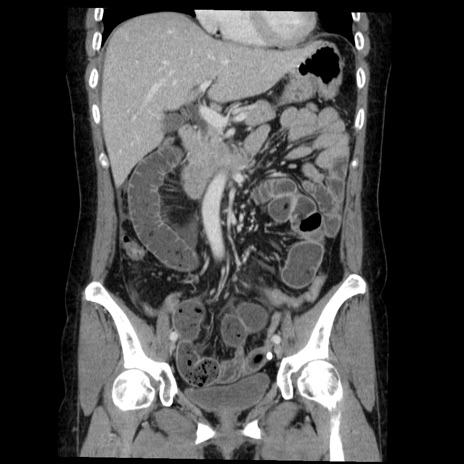

症例6(冠状断像)

【症例】50歳代女性

【主訴】下腹部痛

【現病歴】本日朝より下痢2回あり。 昼食を食べた後、嘔吐3回、下腹部痛認め、症状軽快せず、当院救急搬送。

最終食事:本日昼(生ものなし)。 昨日の夜、刺身を食ぺたとのこと。周囲に同様の症状の者なし。普段、排便は毎日あるとのこと。

【既往歴】卵巣癌術後(8年前に当院で卵巣摘出)

【身体所見】 意識清明、腹部:平坦、腸蠕動音→、やや硬、下腹部自発痛・圧痛あり、反跳痛あり、筋性防御なし。

【データ】WBC 16000、CRP 0.01